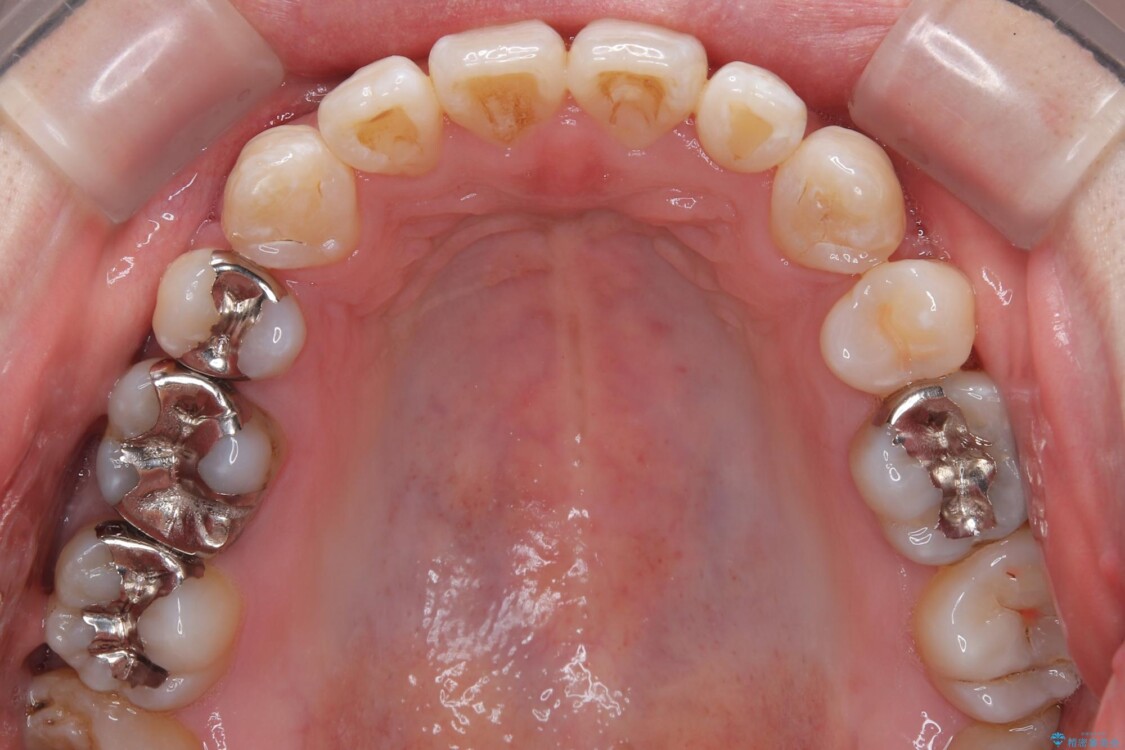

治療前

• 口元の突出感を改善!目立ちにくいワイヤー矯正で自信を持てる自然な横顔に 治療前画像

精密検査の結果、上下左右の小臼歯4本を抜歯し、そのスペースに前歯を後方へ移動させる矯正治療をご提案しました。

装置は、透明感のあるクリアブラケットとホワイトコーティングされたワイヤーを使用した、目立ちにくい審美装置を選択。